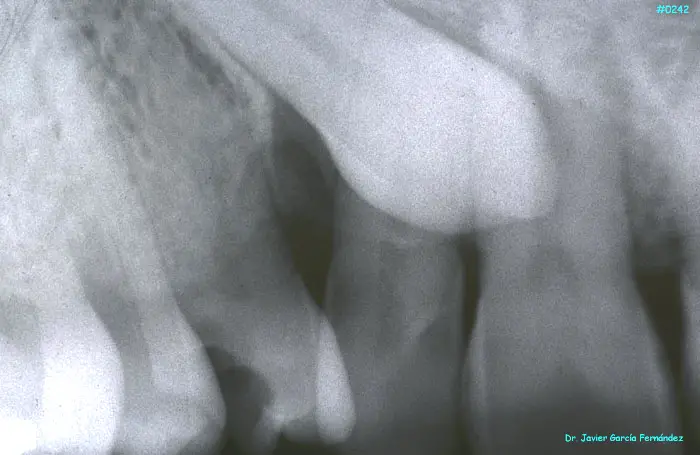

ATLAS DE CIRUGIA PERIODONTAL